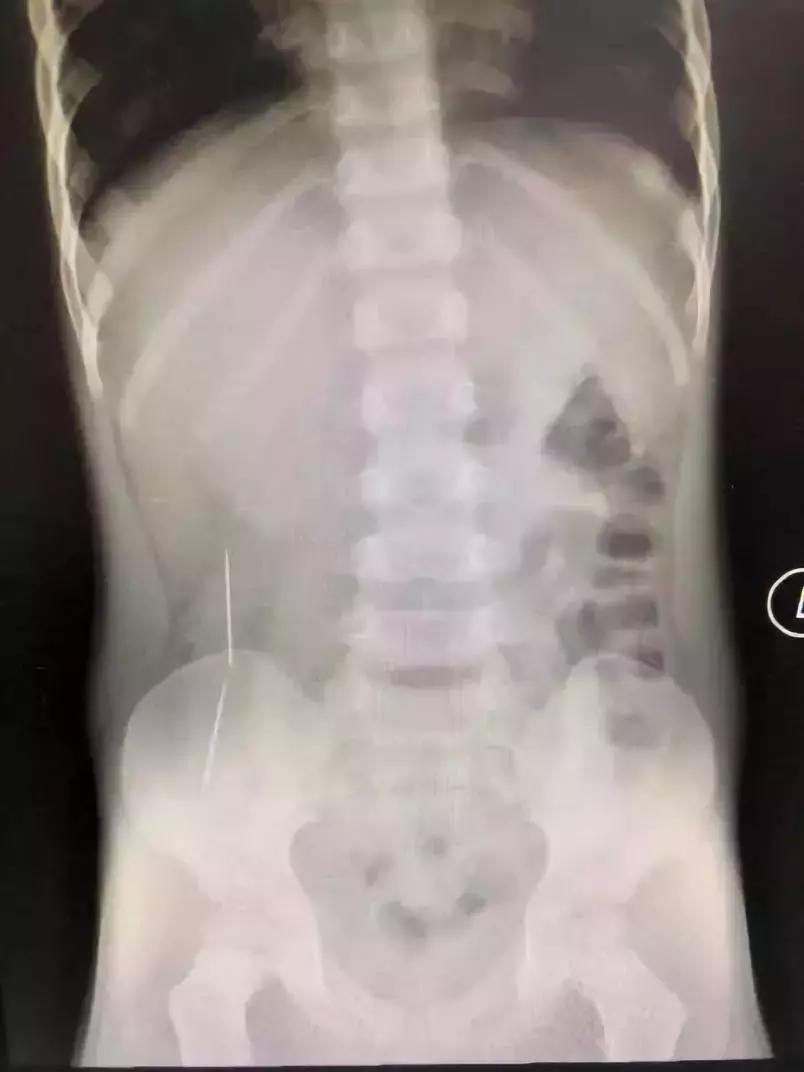

深圳市儿童医院还曾接诊了一位误吞了两条绣花针的小孩彬彬。

彬彬妈妈说,他原本是吃了三根针,有一根因为呛咳当时吐了出来,剩下的两条针就全部吃了进去。

当时,看到X光片,在场所有的人都倒吸一口凉气。而且这两条已在彬彬肠胃穿游数日的绣花针,已穿透了他的肠管造成穿孔,他的腹腔内已造成了感染。情况十分不妙。

好在手术及时,没有造成大量粪便外渗,孩子转危为安。